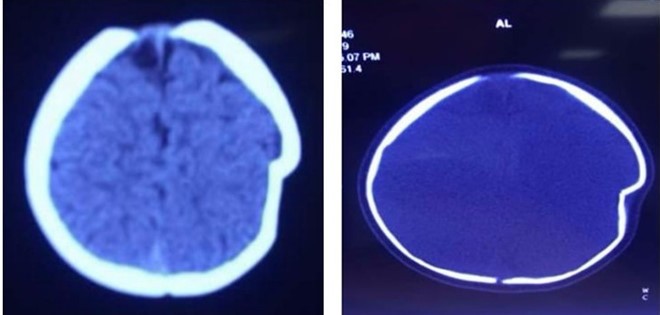

Hình ảnh lún sọ não trước mổ. Ảnh: BSCC.

Thông tin từ khoa Ngoại Thần kinh - Bệnh viện đa khoa tỉnh Phú Thọ - ngày 18/9, cho hay các bác sĩ của khoa đã phẫu thuật để nâng xương lún cho bệnh nhi 8 tháng tuổi bị ngã lún sọ thái dương đỉnh trái.

Mẹ của bé (ở Thanh Thủy, Phú Thọ) cho biết tai nạn xảy ra khi chị để con ngồi trên xe tập đi một mình và không kiểm tra mối dây buộc khiến chiếc xe lao xuống sân với ở độ cao khoảng 1 m. Cú va chạm mạnh với mặt đất đã khiến chóp đầu trái của bé bị lún sâu 1 cm.

Bác sĩ Hà Xuân Tài, Phó khoa Ngoại Thần kinh, bác sĩ trực tiếp phẫu thuật cho bệnh nhi này, cho biết lún sọ thường gặp ở trẻ nhũ nhi dưới một tuổi. Nguyên nhân thường là tai biến sinh có thủ thuật, trẻ bị ngã khi tập đứng, tập đi và ngã ở độ cao thấp. Vị trí thường bị lún ở hộp sọ là vùng đỉnh.

Do ở trẻ nhũ nhi, hộp sọ có khả năng tự điều chỉnh tốt nên hiếm khi phải mổ cấp cứu ngay, trừ những trường hợp lún sọ mức độ nhiều, tổn thương rách màng cứng và tổn thương não. Tuy nhiên, cha mẹ thường rất lo lắng và yêu cầu được mổ ngay vì liên quan đến thẩm mỹ hộp sọ và sợ ảnh hưởng đến thần kinh của trẻ về sau.

Với trường hợp bé 8 tháng này, các bác sĩ đã tiến hành phẫu thuật để nâng xương lún vào ngày 4/9. Đến chiều 12/9, khi sức khỏe ổn định trở lại, bé được xuất viện.